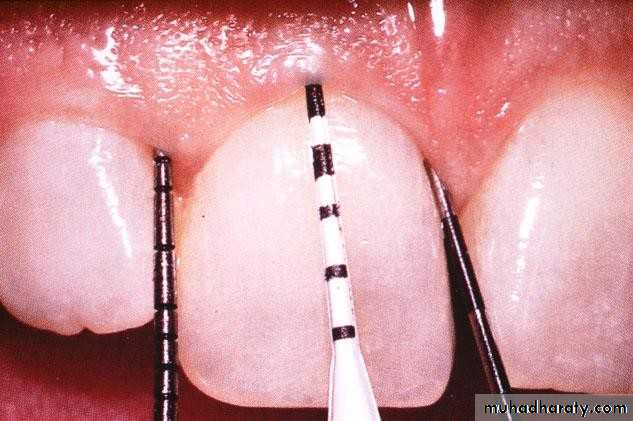

• Periodontal Examination• Probing Depth:

• The distance from the soft tissue (gingiva or alveolar mucosa)

• margin to the tip of the periodontal probe during usual periodontal diagnostic probing.

• the health of attachment can affect the measurement.

• Periodontal Examination Probing

Correct Angulation of Probe• Periodontal pocket

:Clinical Attachment level

Definition:the distance from CEJ to the tip of a periodontal probe (base of the pocket) during usual periodontal diagnostic probing. The health of Attachment apparatus can affect The measurement

• Periodontal Examination

• Clinical Attachment level• Measuring Clinical Attachment Level